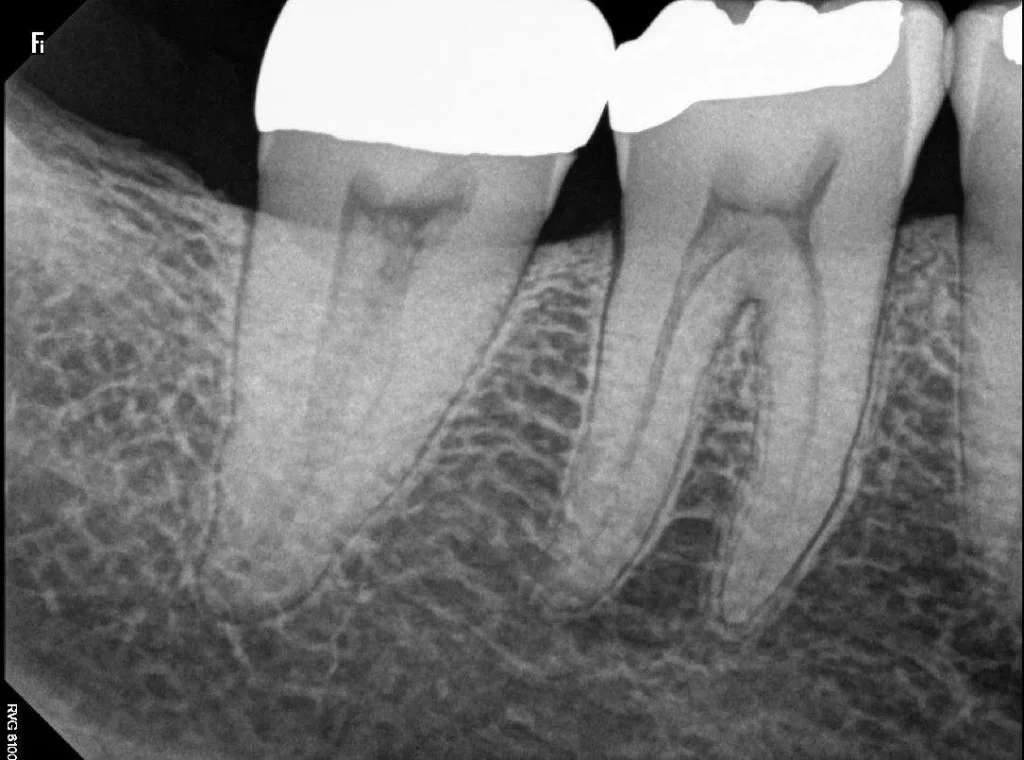

Dental X-rays, also known as radiographs, are images of your teeth that your dentist uses to evaluate your dental and overall oral health. These utilise low levels of radiation to capture pictures of the insides of your teeth and gums. This can help your dentist to recognise problems, like cavities, tooth decay, and impacted teeth.

There are two types of dental X-rays – the intraoral and the extraoral X-rays.

Intraoral X-rays

Involve the digital imaging of the teeth, your bite, and gums.

Periapical X-ray

This technique concentrates on two complete teeth from the root to crown.

Your Preston dentist will review your X-rays and check for irregularities. If your dentist spots problems, such as cavities or tooth decay, they’ll discuss your treatment options.